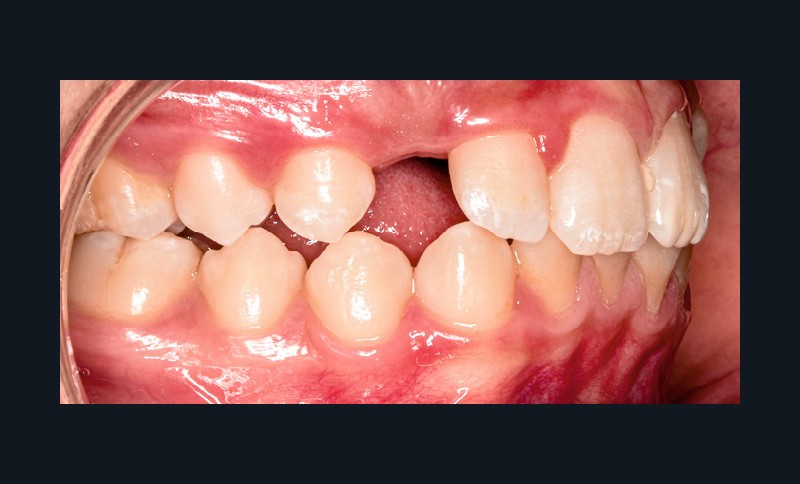

Sur le plan alvéolo-dentaire (fig. 1b) :

- Classe II subdivision gauche avec déviation du point inter-incisif mandibulaire à gauche ;

- occlusion inversée entre 22 et 32 ;

- dysharmonie dento-arcade (DDA) sévère ;

- 13 en position haute retenue.

Sur le plan squelettique : Classe II, schéma hypodivergent (fig. 1c). Sur le plan fonctionnel : aucune dysfonction ni parafonction.